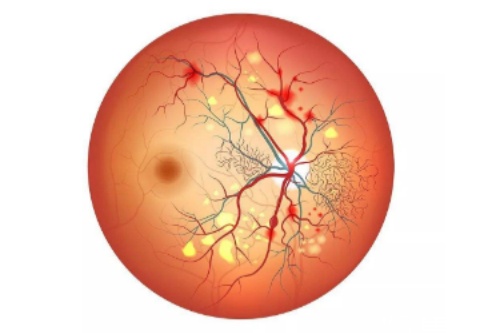

黄斑前膜手术旨在去除视网膜黄斑区增生性膜以改善视力,手术过程精细且需高度专注。

首可靠行玻璃体切除,清除眼内玻璃体以提供清晰视野;随后使用特定染色剂(如亮蓝)使黄斑前膜显色,便于比较准操作。

在显微镜下,医生用精细工具(如视网膜钩或镊子)小心抓住并剥离前膜,尽量减少对视网膜的损伤。

剥除后,详细检查视网膜表面是否有残留膜,并清理干净。然后,向眼内注入平衡盐溶液维持眼球形状,闭合切口。